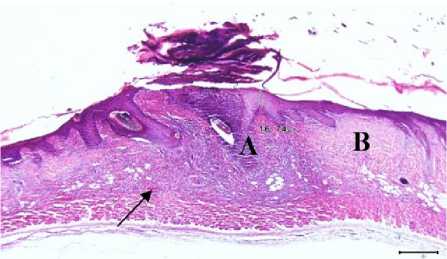

Gambar 3. Gambaran mikroskopis kulit tikus putih kelompok perlakuan II (diberi gerusan daun pegagan) hari ke tujuh. Terlihat adanya infiltrasi sel radang (A), proliferasi fibroblast (B) dan neovaskularisasi (tanda panah) (HE, 100x).

Hasil pengamatan tikus kelompok II pada hari ke tujuh untuk pengamatan sel epitel sebagian besar menyebar dengan kepadatan rendah dan terdapat 1 sampel yang belum terbentuk epitel. Pembuluh darah baru yang terbentuk menyebar dengan kepadatan tinggi dan sel radang sebagian besar menyebar dengan kepadatan sedang. Gambaran mikroskopis tikus putih kelompok perlakuan I dan II pada hari ke tujuh dapat dilihat pada Gambar 1, Gambar 2, Gambar 3 dan Gambar 4.